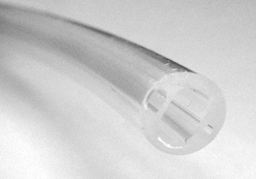

After TURP or prostatectomy, the two eyes under the ballon improves the drainage of the Urine and the blood from the bladder neck.

Large Diameter ( 18 to 24 Fr )

allow for large chunks of debris to pass through the catheter

100% Silicone

Clear catheter body

Closed Round Tip

Large bevels and eyes

Wide irrigation and drainage Channels

Wide Irrigation and Drainage Channels